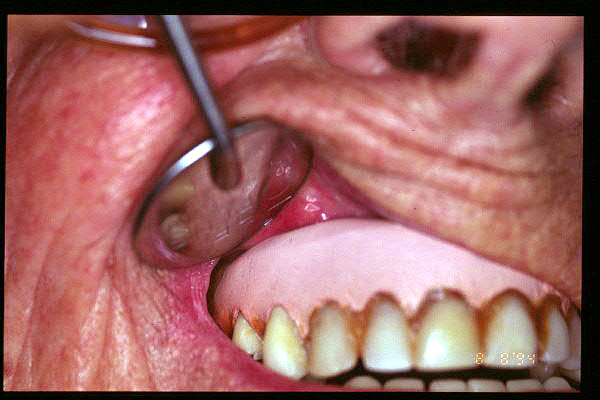

CM Hiperplasis por prótesis mal adaptada